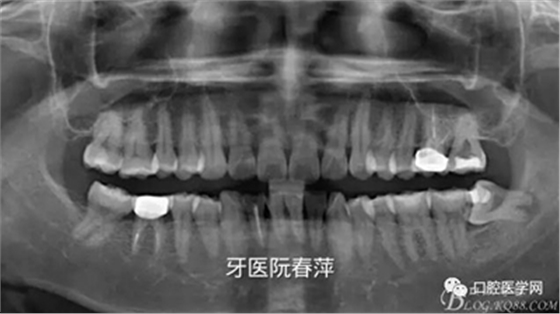

戴牙后全景片:

絢彩AT無飾瓷全形態(tài)氧化鋯產(chǎn)品體驗(yàn)+全冠和嵌體微創(chuàng)修復(fù)后牙

后牙的修復(fù)體X光線阻射應(yīng)該強(qiáng)于釉質(zhì),以方便日后對繼發(fā)齲的檢查。X光片還能從直觀上對修復(fù)體邊緣是否密貼,鄰面有無懸突進(jìn)行進(jìn)一步的檢查。